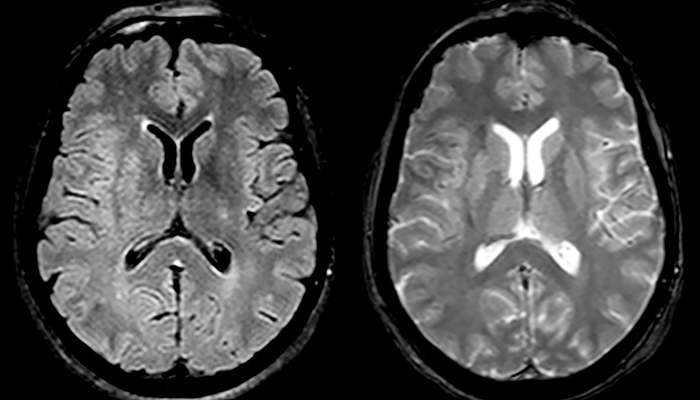

“Ingenia 3.0T provides us very good image quality with high SNR, even if we push the resolution. For example, in FLAIR images we may have an isotropic resolution of 0.9 mm. Ingenia allows us to use 3D T1 TSE with BrainView, which has a better sensitivity than 2D spin echo imaging[2] and 3D gradient echo imaging. Ingenia also provides highly reproducible exams, which is important in MS imaging so that follow-up exams at different time points are done the same way.”

For MS imaging in the brain, Dr. Savatovsky uses 3D FLAIR as the basic sequence to visualize the lesions and assess the situation and lesion load. “We count the lesions in each location to determine if the criteria of the disease are fulfilled. We use a T2-weighted sequence because our neurologists are used to it. We compare the lesion load on FLAIR with a 3D T1 post-contrast sequence to help us determine whether lesions are old or new. We typically administer the contrast before the patient enters the machine because it shortens the examination time and allows to visualize active lesions that tend to be more visible after several minutes. When a differential diagnosis is difficult, we add sequences such as susceptibility imaging, because some focal MS lesions have a small vein in the center[3].”